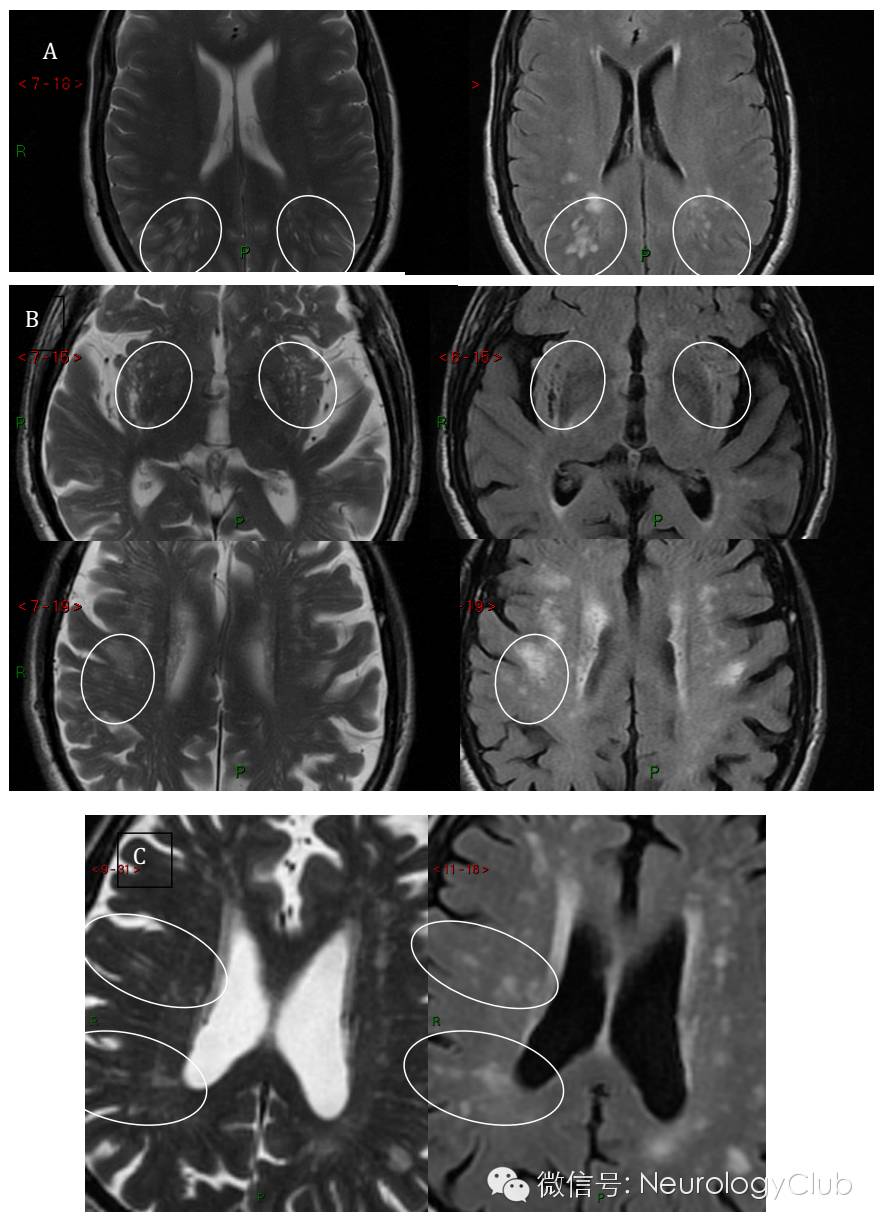

(A:72岁无症状患者,T2WI可见线状血管周围间隙,FLAIR可见血管周围间隙旁白质高信号;B:49岁男性,T2WI可见左侧内囊急性小梗死[未放图]和从脑室旁延伸至皮质下组织的血管周围间隙;C:相应的FLAIR上一处白质高信号位于血管周围间隙旁;D:组织学上的血管周围间隙,可见小穿支动脉旁脑实质回缩。多为老年脑的典型表现,常伴有CSVD

(T2WI[左]可见边缘薄而锐利的白线状和点状血管周围间隙;FLAIR[右]可见较大蓬松的白质高信号,在个别案例中位于血管周围间隙旁。指示的部位已用圆圈出。B的上图中,基底节区外囊部位血管周围间隙在T2WI上表现为低信号区域)